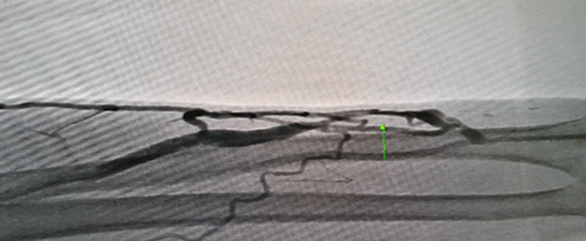

풍선시술 시술 후

투석혈관 관리와 치료하기 투석혈관

풍선시술 시술 전